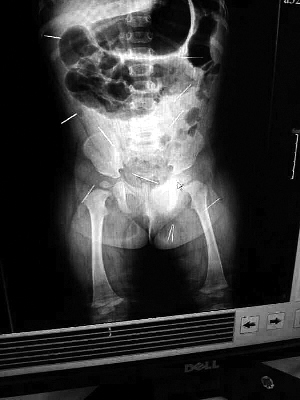

山东聊城11个月女婴萱萱(化名)疑似被人以12根钢针插满臀部、腹腔等部位,昨天在儿童医院会诊后,医生称3根针靠近胸腔最危险,首批先行取出,预计将在下周二手术。孩子父母称孩子一直由家人照顾,自家与他人并无冤怨。山东警方表示正在侦破中,不便透露案情。

北京晨报记者了解到,目前体内的12根钢针多分布在孩子的臀部,一根在腹部,其余3根在胸腔附近,其中一根很接近心脏(如图)。“因为孩子太小,医生们害怕取针的时候对她造成伤害,在胸腔附近的3针可能会威胁她的生命”。

截至昨晚6时许,北京晨报记者从儿童医院宣传部门了解到,孩子目前已经接受完专家会诊,暂定今天和下周一进行术前检查,如果一切顺利将在下周二手术,“孩子暂时没有生命危险”。